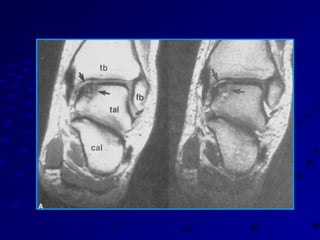

MRI shows marrow edema, and effect onMRI shows marrow edema, and effect on

the surrounding bonethe surrounding bone

CT gives a more accurate sizing of theCT gives a more accurate sizing of the

lesionlesion

Arthroscopy accurately defines the lesionArthroscopy accurately defines the lesion

and determines therapeutic approachand determines therapeutic approach